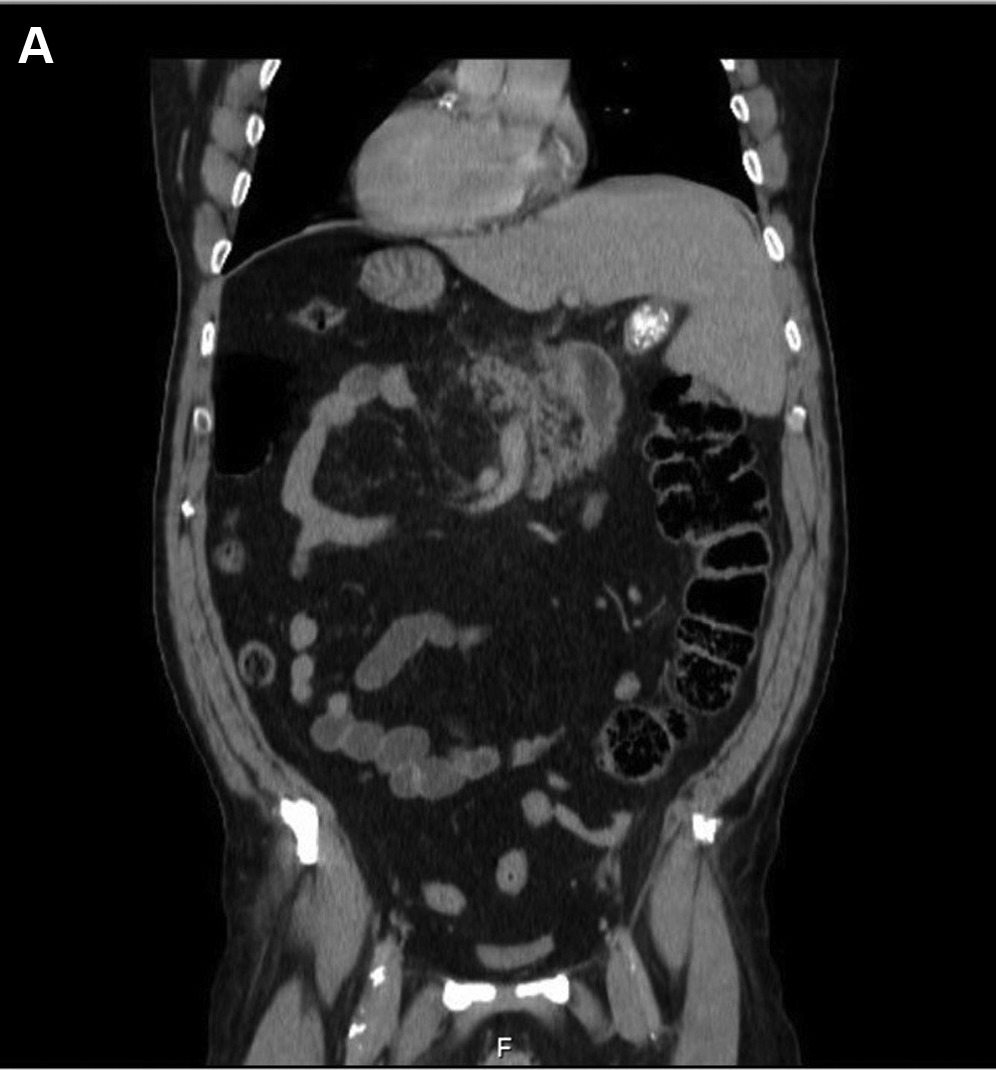

@AGA_Gastro Cholecystitis with Cholelithiasis